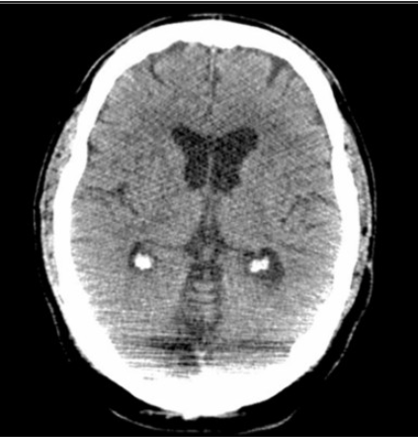

The streak artifact in this case is caused by the arms of the patient being in above the head position and outside the scan FOV.

When anatomy or anything else somewhat dense (IV bags, monitoring equipment) is outside the scan FOV, it will only be seen by the scanner on some projections (incomplete projection artifact) and cause errors in the reconstruction, resulting in streaking. The geometry of the streak artifact converges outside the FOV and not at the calvarium and thus cannot be beam hardening artifact, which would be more pronounced at lower kVp settings.